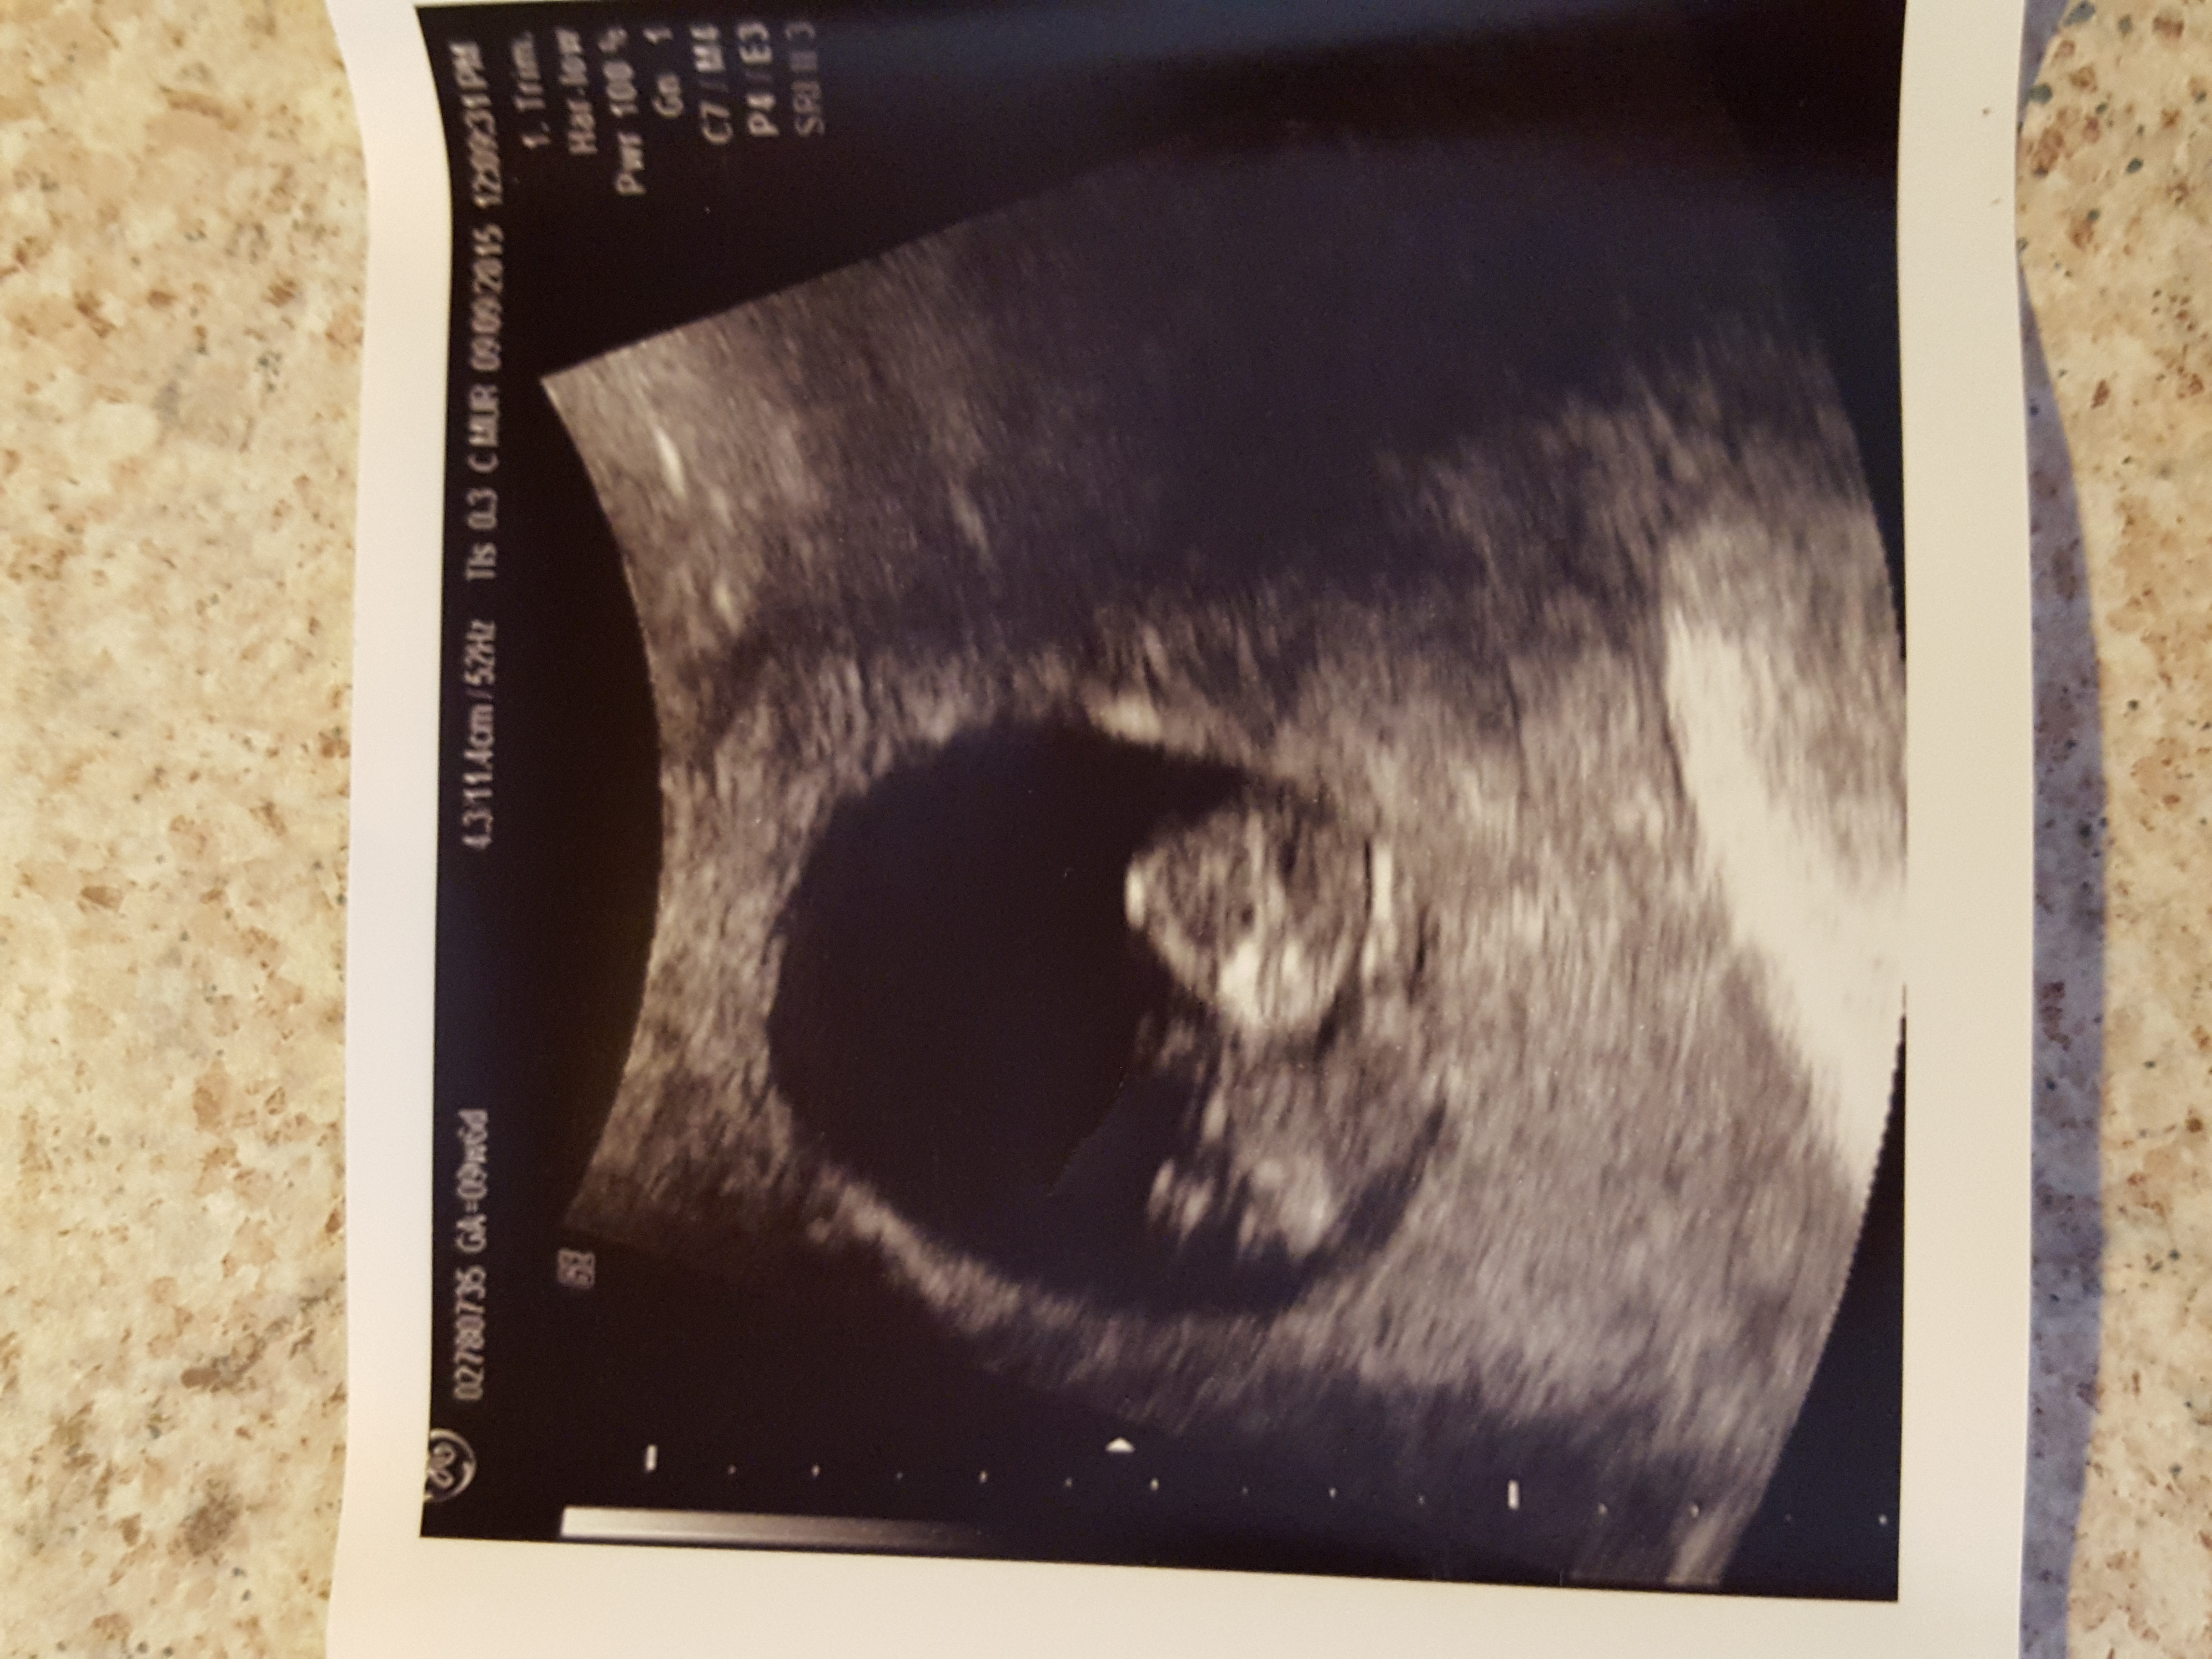

• Our little gummy bear today at 9w2d with a heart rate of 172 :)